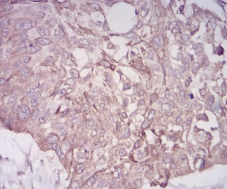

IHC    1/200 - 1/1000